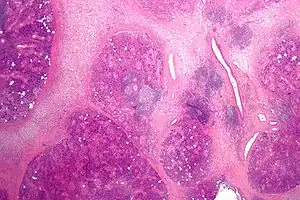

Microanatomy

The gland is internally divided into lobules. Blood vessels and nerves enter the glands at the hilum and gradually branch out into the lobules.

Acini

Secretory cells are found in a group, or acinus. Each acinus is located at the terminal part of the gland connected to the ductal system, with many acini within each lobule of the gland. Each acinus consists of a single layer of cuboidal epithelial cells surrounding a lumen, a central opening where the saliva is deposited after being produced by the secretory cells. The three forms of acini are classified in terms of the type of epithelial cell present and the secretory product being produced - serous, mucoserous, and mucous.[18][19]

Ducts

In the duct system, the lumina are formed by intercalated ducts, which in turn join to form striated ducts. These drain into ducts situated between the lobes of the gland (called interlobular ducts or secretory ducts). These are found on most major and minor glands (exception may be the sublingual gland).[18]